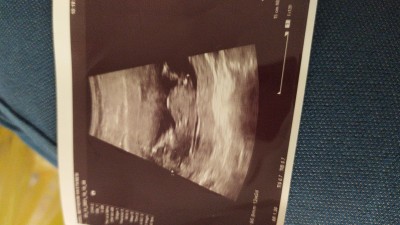

12+6cinsiyet tamini

Cinsiyet tahmini kizlar12+6

Gebelik haftası

12+6

Erkek keselerinde bebeğin keseye yattığı yerde boşluk oluyor ve popo biraz havada görünüyormuş. Kızlar ise keseye yapışık oluyormuş ve popo düz oluyormuş. Bu bilgiye göre bence kız :) Allahu âlem :)

Erkek bebek keseden öyle düşünüyorum

Kiz bence tabi doktor bilir doğrusunu